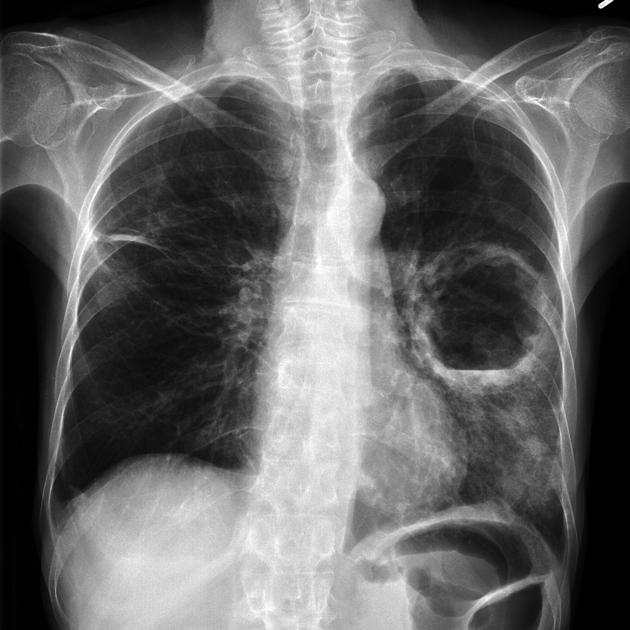

Ключевым этапом протокола является рентгенография органов грудной клетки в двух проекциях, которая позволяет визуализировать очаг инфильтрации с уровнем жидкости и газовой полостью — характерный признак сформированного абсцесса. Обследование проводится в прямой (постеро-антериальной) и боковой проекциях грудной клетки, при необходимости дополняется прицельной съёмкой поражённых сегментов и рентгеноскопией для оценки уровня жидкости. Применяются стандартный режим для оценки общего состояния лёгочных полей и средостения и высококонтрастный режим для выявления тонких стенок полости, уровня жидкости и сопутствующих фиброзных изменений. Рентгенография позволяет выявлять прямые признаки абсцесса лёгких, указывающие на наличие полостного образования с жидкостью, а также косвенные признаки и рентгенологические сигналы, свидетельствующие о длительном воспалительном процессе и ремоделировании лёгочной ткани.

Рентгенография выявляет следующие признаки абсцесса легких:

- Полость округлой или овальной формы с утолщёнными и неровными стенками, преимущественно в верхних или задних сегментах (прямая проекция, стандартный режим).

- Горизонтальный уровень жидкости с чёткой линией раздела газа и жидкости — рентгенологический сигнал, характерный для абсцесса (боковая проекция, прицельная съёмка).

- Уплотнение лёгочной ткани вокруг полости с формированием фиброзных тяжей (боковая проекция, высококонтрастный режим).

- Смещение прилежащих бронхиальных структур, бронхоэктазы в зоне хронического воспаления (прямая проекция, стандартный режим).

- Косвенные признаки: деформация контуров плевры, подъём купола диафрагмы, смещение средостенных структур в сторону поражения (боковая проекция, прицельная съёмка).

Рентгенограмма даёт возможность детально визуализировать следующие диагностические параметры абсцесса легких:

- Локализация полости по долям и сегментам лёгкого.

- Размеры полости, толщина и характер стенок (гладкие, неровные, кальцинированные).

- Наличие и высота уровня жидкости, характер газового содержимого.

- Структурные изменения окружающей лёгочной ткани, включая фиброз, бронхоэктазы и деформацию сосудистого рисунка.

- Косвенное влияние на объём и вентиляцию поражённого участка.